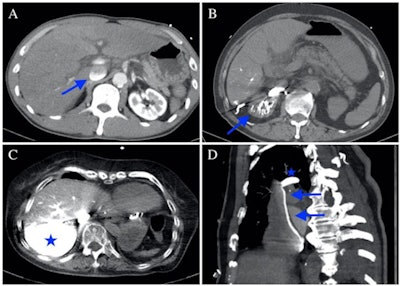

The CAP sign shows the effect of gravity, the group explained in the article posted on 6 May.

"The density of contrast agent is much higher than that of blood; thus, during normal physiological blood flow, specific gravity has little effect on the contrast agent dynamics," the team wrote. "In patients with cardiogenic shock or impending circulatory collapse, both the arterial and venous blood flow dramatically decreases, and the contrast agent tends to accumulate in the dependent parts of the venous system."